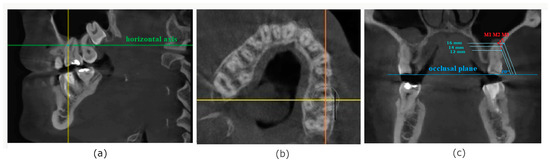

2.3. Palatal Bone Thickness Measurements

Modified palatal height index was also calculated as a relation between the height and width of the palate according to the formula:

Modified   palatal   height   index   = Palatal   height   × 100 % Palatal   width

For the purpose of this measurement, coronal slice of CBCT was selected, when the coronal axis was set at the center of the crown of the first molar. Although to calculate palatal height index [13] the distance between palatal cusps of the first maxillary molars should be used, for the purpose of our study, palatal width was defined as the horizontal distance between alveolar ridges on the palatal side of the right and left first maxillary molar to eliminate the influence of the inclination of these on the result (Figure 2). The perpendicular distance between the midpalatal raphe and the occlusal plane was measured to evaluate palatal height.

Figure 2. Measurement of modified palatal height index: (a)—horizontal slice used to obtain coronal view, (b)—measurements of the palatal width and height.